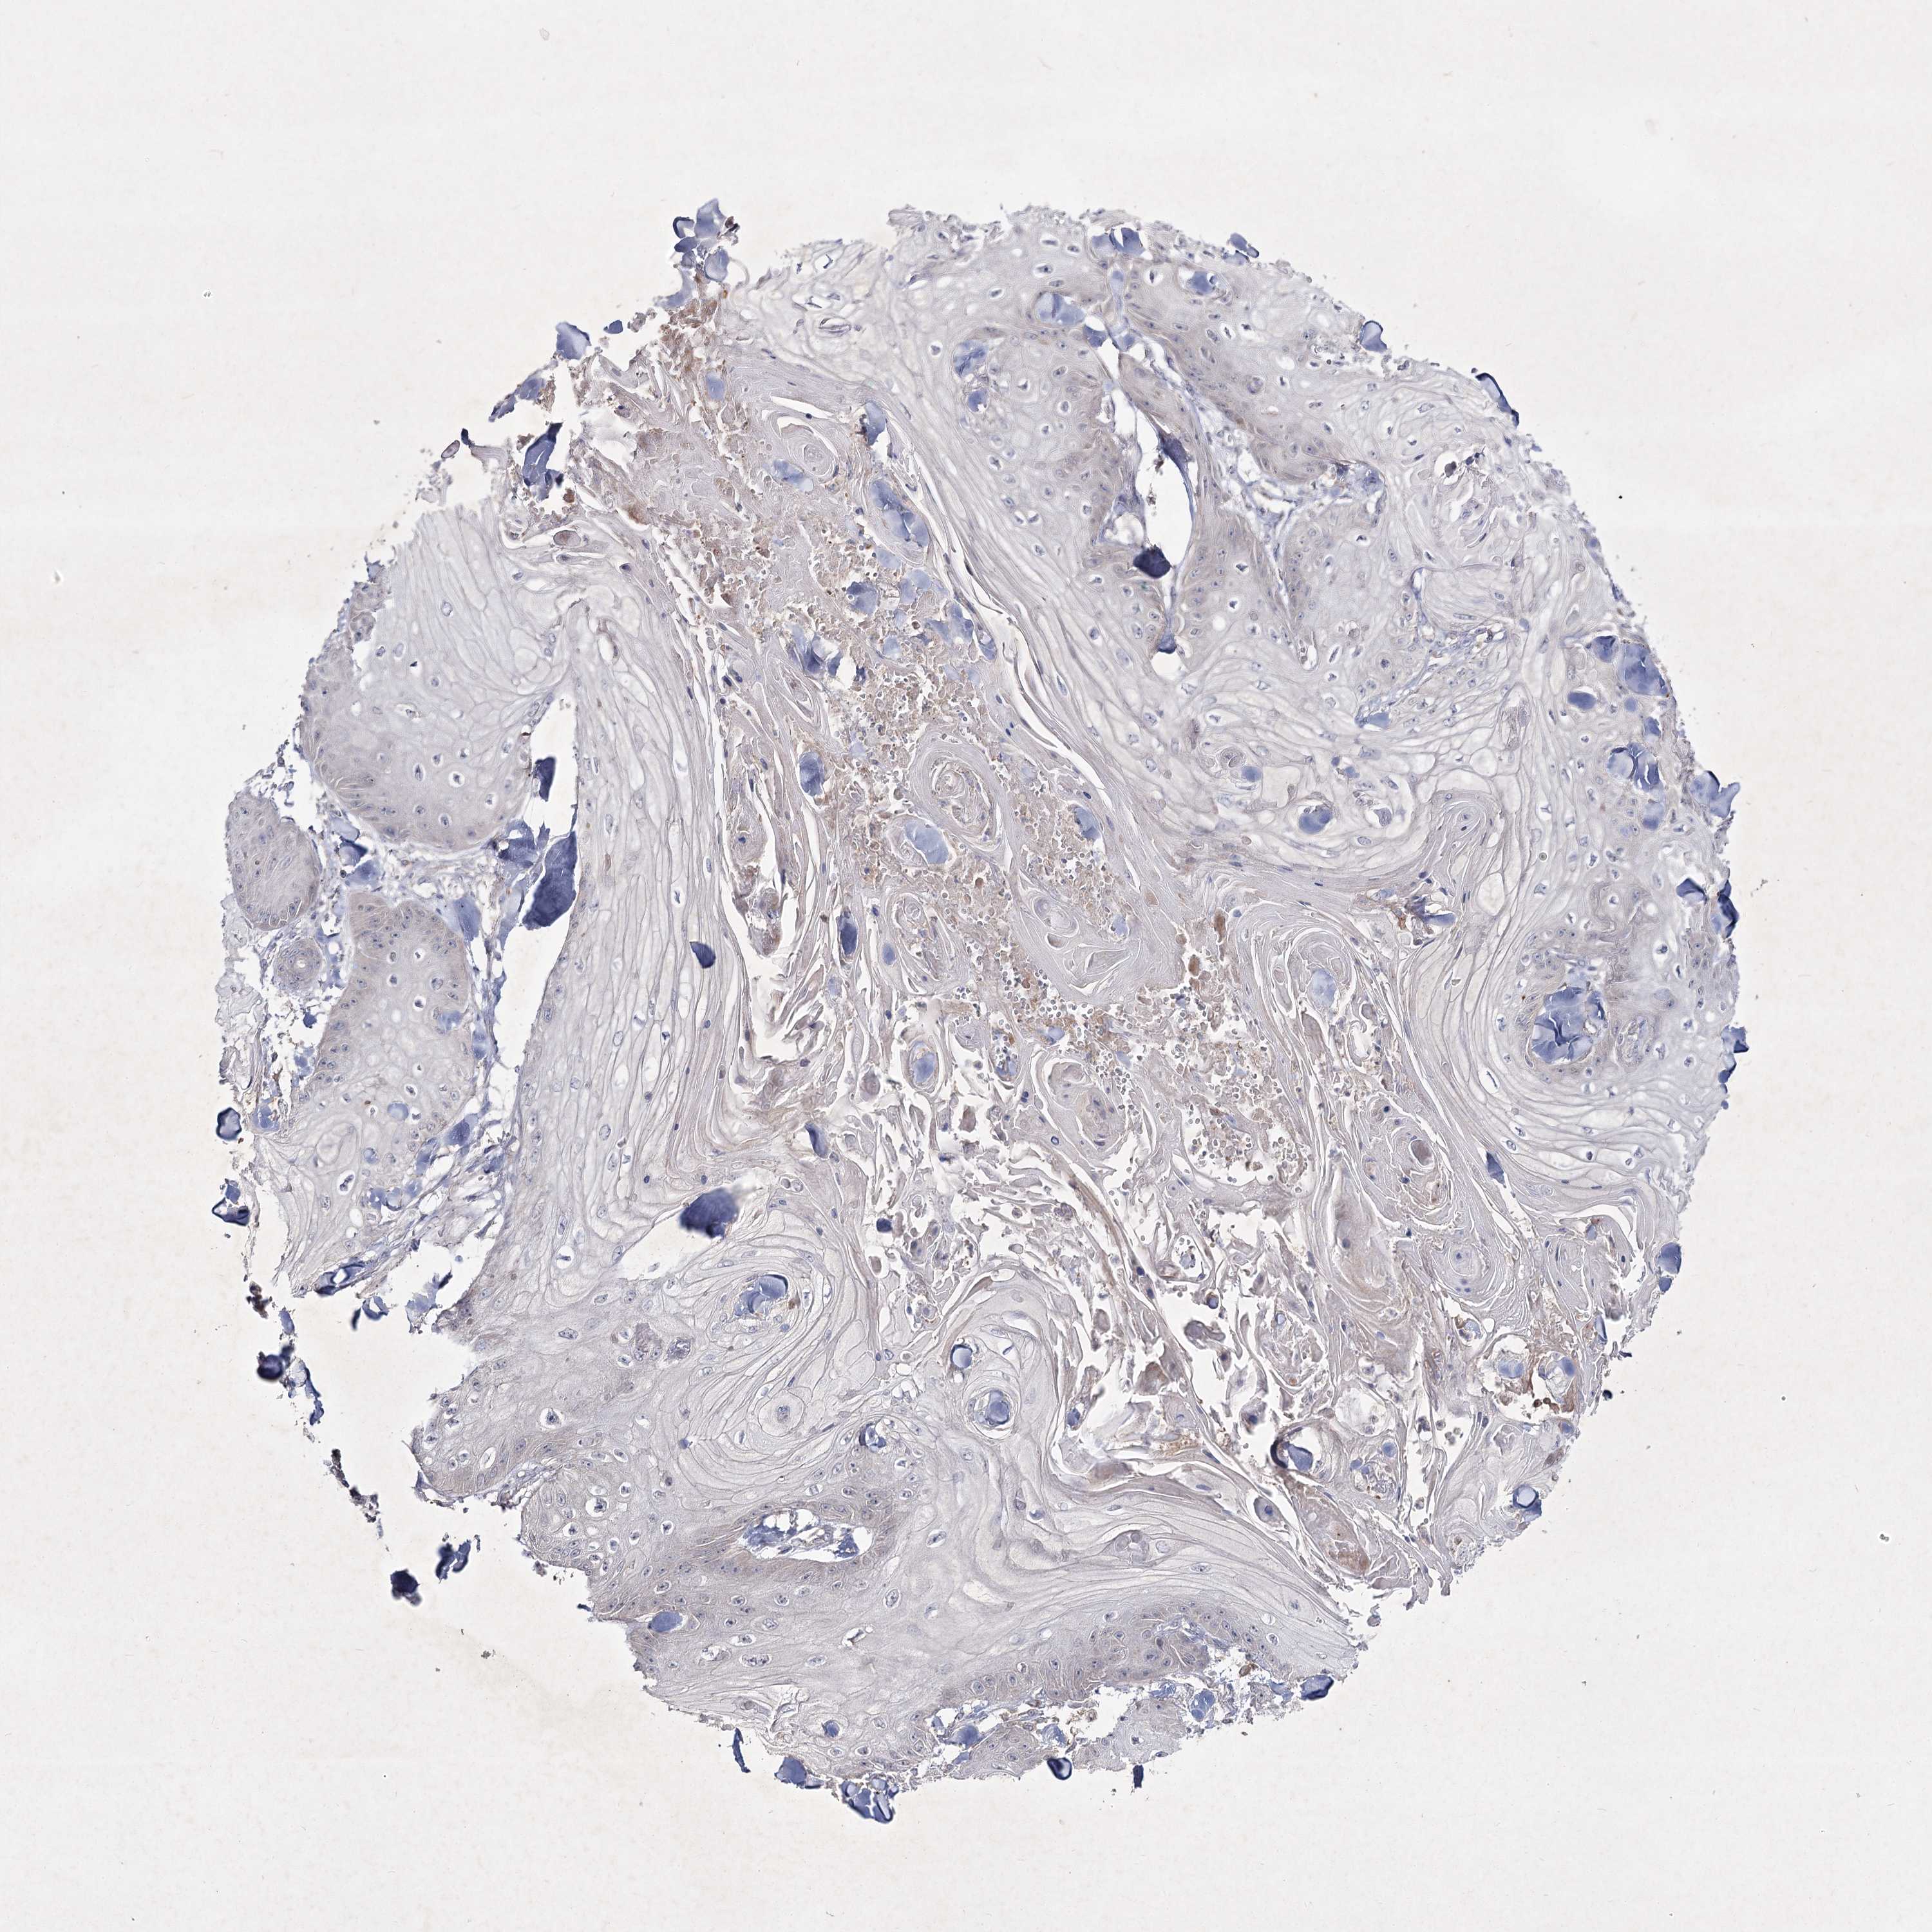

Basal cell and squamous cell cancer

SKIN CANCER - Protein expressioni

A mouse-over function shows sample information and annotation data. Click on an image to view it in a full screen mode. Samples can be filtered based on level of antibody staining by selecting one or several of the following categories: high, medium, low and not detected. The assay and annotation is described here.

Antibody stainingi

Antibody staining in the annotated cell types in the current human tissue is reported as not detected, low, medium, or high, based on conventional immunohistochemistry profiling in selected tissues. This score is based on the combination of the staining intensity and fraction of stained cells.

Each image is clickable and will lead to virtual microscopy that enables deeper exploration of all samples and also displays staining intensity scores, fraction scores and subcellular localization as well as patient and tissue information for each sample.

Antibody HPA036697

Staining

High

Medium

Low

Not detected

Intensity

Strong

Moderate

Weak

Negative

Quantity

>75%

75%-25%

<25%

None

Location

Nuclear

Cytoplasmic/membranous

Cytoplasmic/membranous,nuclear

Squamous cell carcinoma, metastatic, NOS

Squamous cell carcinoma, NOS